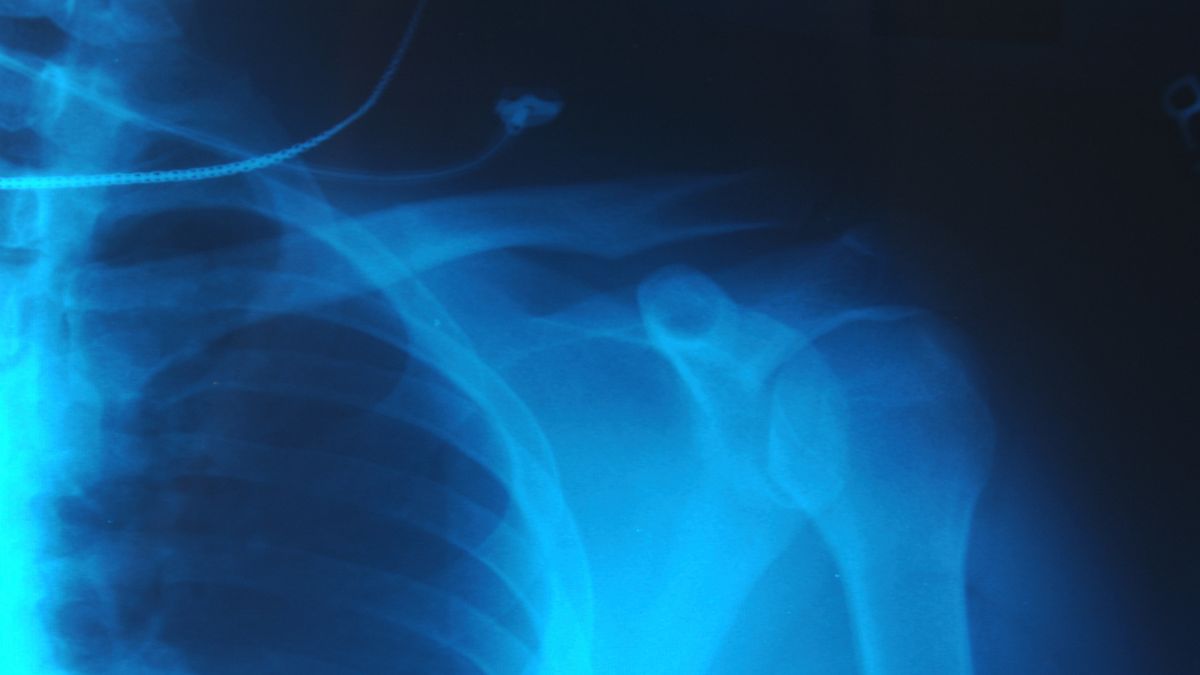

Musizierende sind durch ihre intensive und repetitive Belastung häufig von akuten oder chronischen Schmerzen betroffen, insbesondere an Händen, Schultern und Ellenbogen. Die Univ.-Klinik für Strahlentherapie – Radioonkologie bietet spezialisierte Behandlungsoptionen an, darunter die niedrigdosierte Bestrahlung zur Linderung von Schmerzen bei Arthrose, Sehnenentzündungen (z. B. Tennis- oder Golfer:innen-Ellenbogen) und Fibromatosen wie Morbus Dupuytren. Diese Therapie kann helfen, Beschwerden zu reduzieren und die Funktionalität der betroffenen Gelenke zu erhalten.